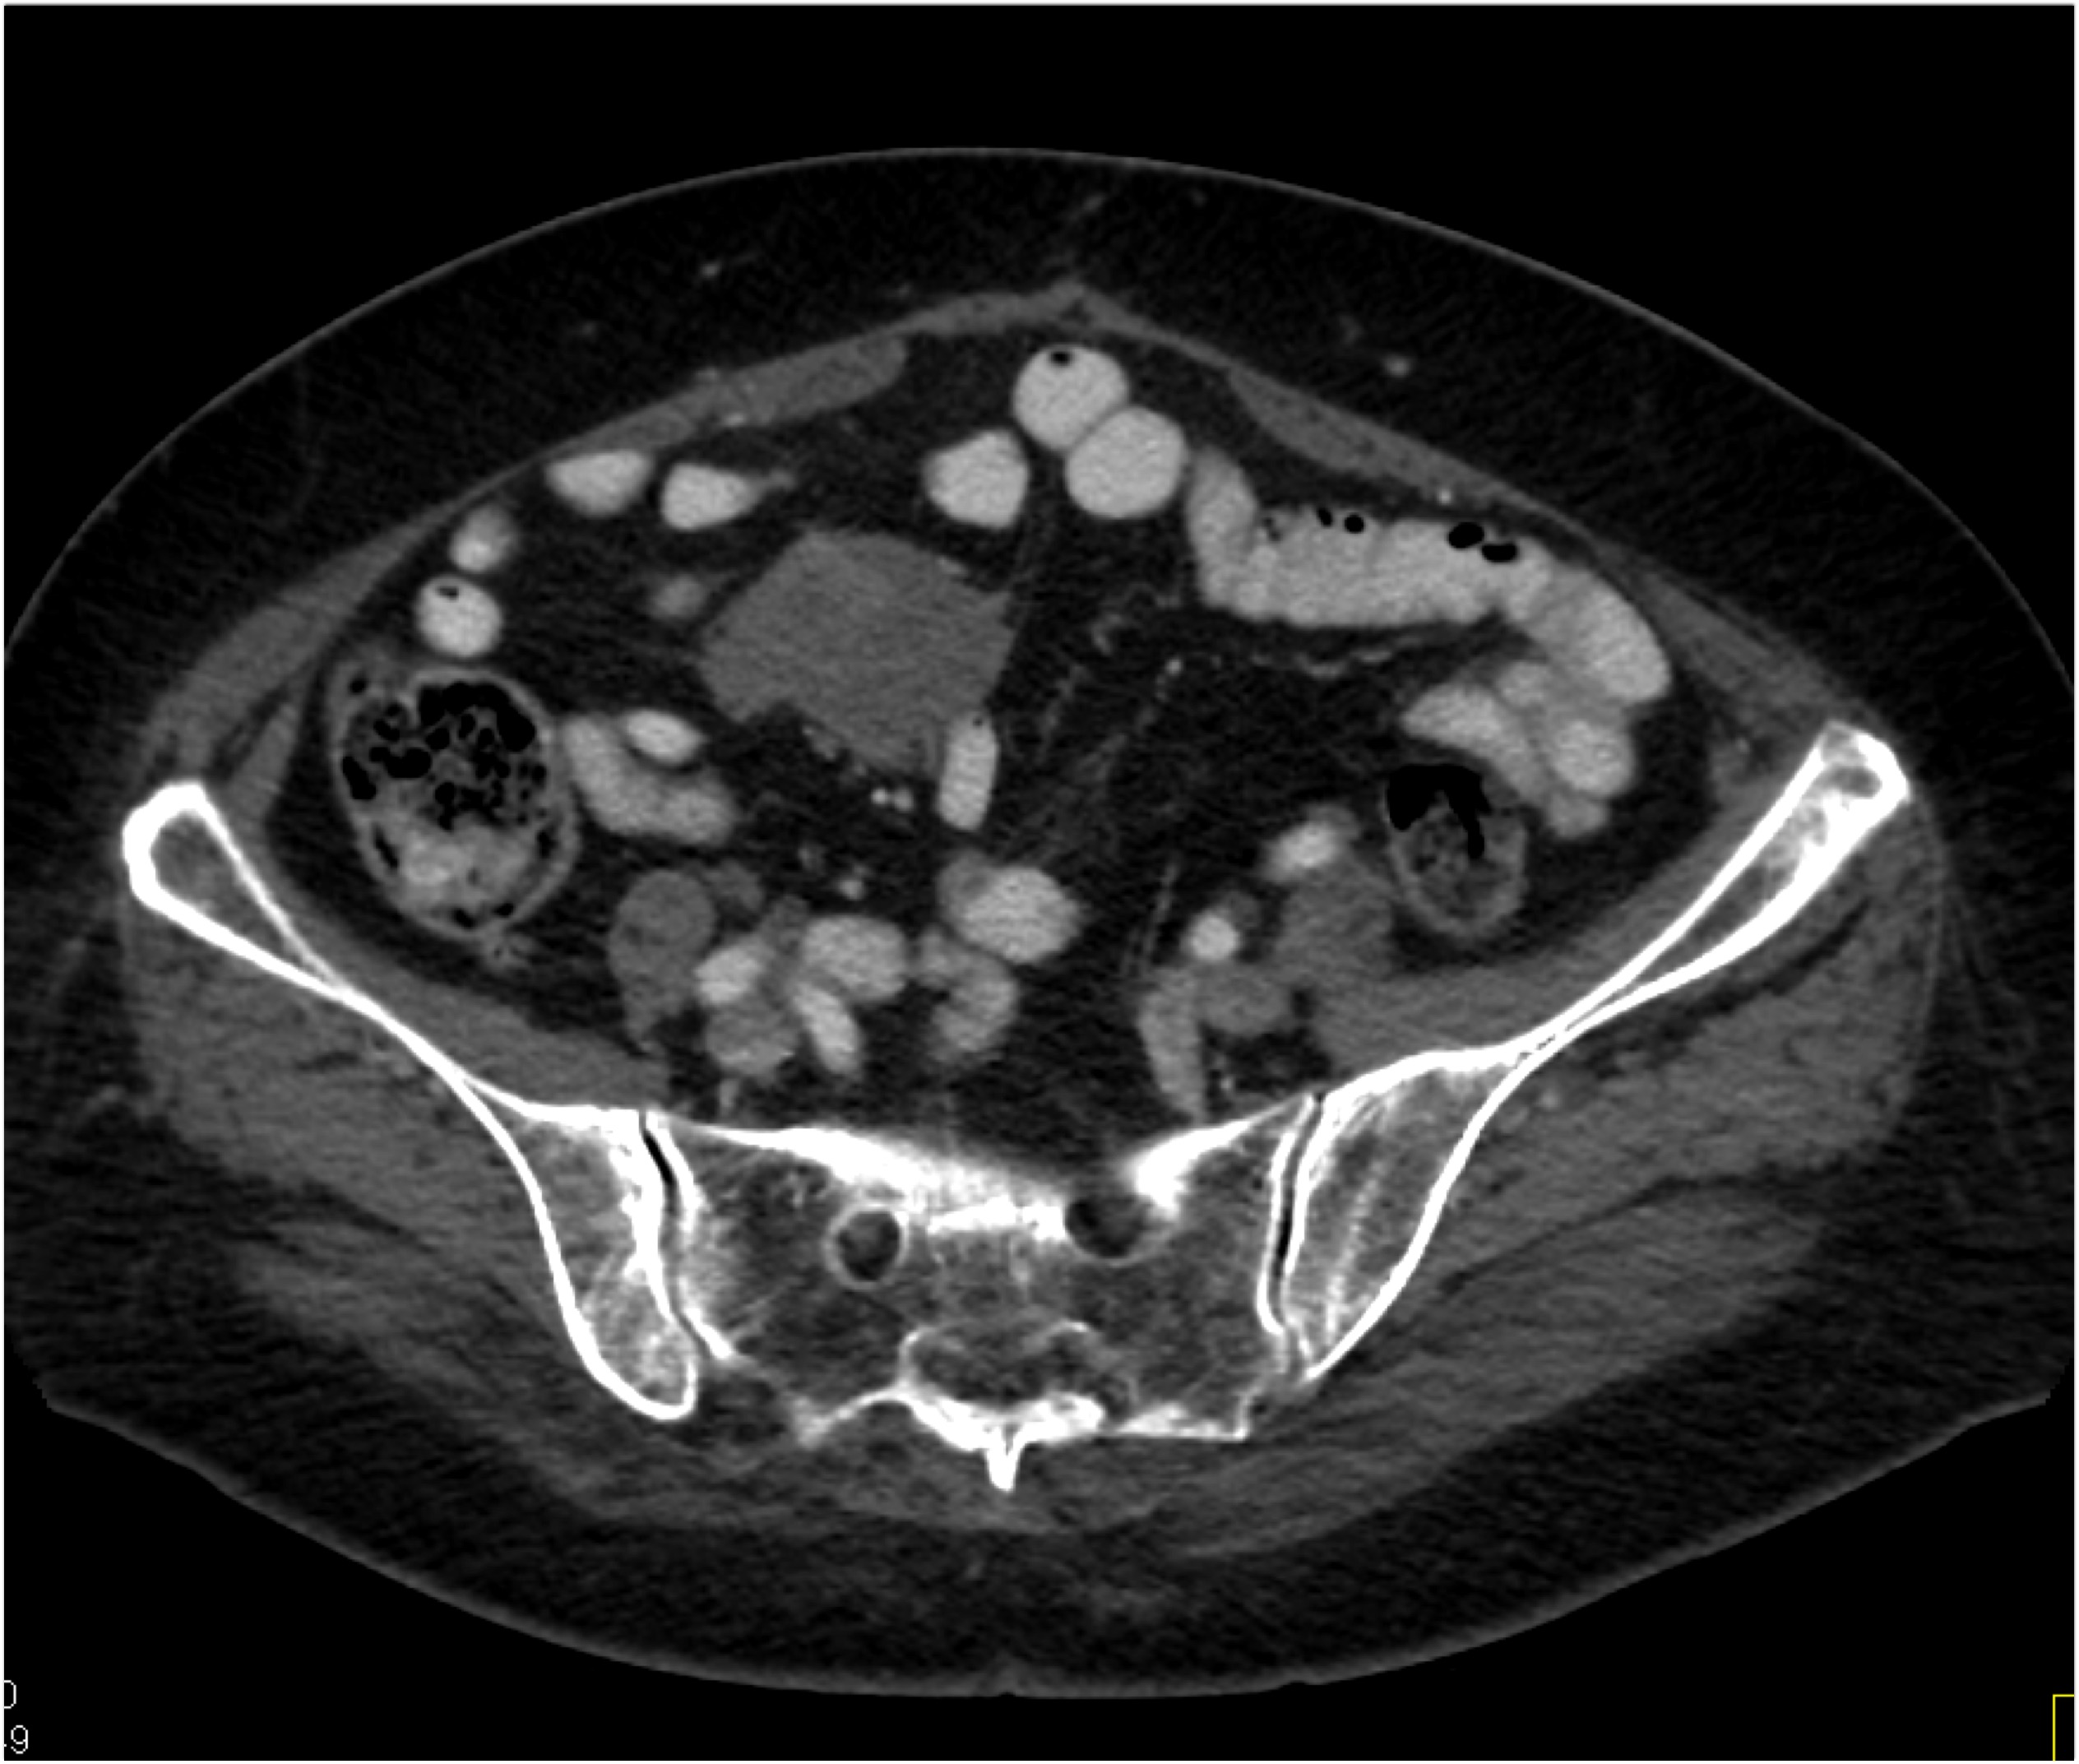

7) In this patient with pelvic pain the best diagnosis is?

lymphoma

silicon injection into buttocks

neurofibromatosis

intramuscular hemorrhage